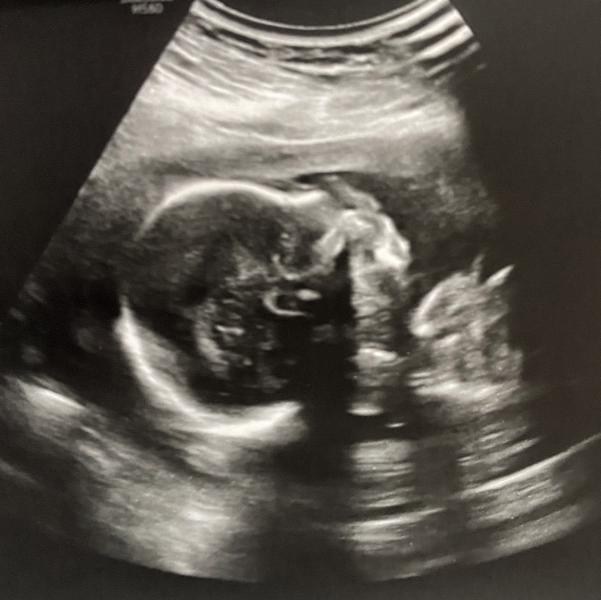

Делала сегодня второй скрининг у Глебова в «Медсонар». Подтвердил мальчика (на втором фото обведён сердечком наш писюн🤣). У малыша всё хорошо, 357 гр😅 Опережает развитие на несколько дней и поэтому пдр ставят на 2 мая, а не 6-е. Сидит на попе))